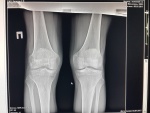

Снимки Все почему то не прикрепляются(пишет ошибка - прикрепите изображение)-прикрепил только снимок октября 2016г. Все снимки в положении лежа. Поэтому ссылка: Ренген снимки (август 2016 (на следующий день после начало жалоб на не устойчивость), октябрь 2016, январь 2016г.) ссылка на этот файл: http://my-files.ru/dia0c4

Мужчина 40 лет, 178 см, 82 кг, офисная работа. Боли впервые (ранее никогда не беспокоили)возникли в начали августа 2016г. при обычных приседаниях -скованность в правом колене, (через несколько дней боли по суставной щели с внутренней стороны, вначале в правом, через неделю в левом колене) , через 2-3 недели очень резко усилились боли, при спуске -подъеме на лестнице. И появилась сжение под коленными чашечками, чувство сдавливания по суставным щелям и сразу -неустойчивость в коленях, не возможность поднять любой вес 2-3 кг (сразу сильные боли в коленях), в положении лежа боли при выпремлении правого колена. За 2-3 мес. до болей занимался сидя -лежа (стоя не занимался) с гантелями на спорт.скамье, прямых травм во время занятий и ранее не было. В юности занимался любительским футболом, баскетболом, - периодически с гантелями (штангой стоя и приседаниями с весом -ни когда не занимался), -травмы колен отрицает. Периодически был незначительный хруст (без болей и дискомфорта). Лечился с августа 2016г. у ортопедов - травматологов (мази, компрессы с демексидом, физио: магнит, лазер, уколы в/м: Эльбона, вольтарен, Артра, уколы в/с гиалуроновой кислоты, затем снова в/м дексаметазон)-без эффекта, ухудшение. С конца августа по рекомендации врача - носил эластичные бинты - наколенники, со слов -без них вообще не мог стоять, с конца октября -с тростью. Сдавал за этот период несколько раз анализы ОАК, мочи, ревмопробы)-все в норме. Снимки сделаны три раза за период с августа 2016г. по январь 2017г. -резкое прогрессирование заболевания. Ваше мнение по снимкам. Также,по собственной инициативе, делал МРТ три раза за этот период (если необходимо -будет ссылка на файлообменник)

Снимки

Не к чему придраться. Разве сужение суставных щелей. Рекомендуйте МРТ, в крайнем случае УЗИ.

А на снимках тоже ничего потрясающего не нашла. Минимальные признаки артроза, лигаментоз крестообразных связок. Может, не в коленях причина а в позвоночнике?

На правом к.с. после разных обследований сделали артроскопию в конце ноября 2016г. Ситуация такая, что человек с начала марта 2017г. практически не может ходить (быстрое прогрессирование заболевания, в начале августа первые боли - затем через 2-3 недели , неустойчивость в коленях и только в эластичных наколенниках ходьба, в середине октября -только с тростью ходьба и далее ухудшение (с августа без нагрузок, с октября -больничный).С января 2017г. -полужеский Артез и трость. В январе 2017г. по КТ пятнистый остеопороз. С начала заболевания делали по три раза Ренген.снимки, МРТ, что за заболевание такое?